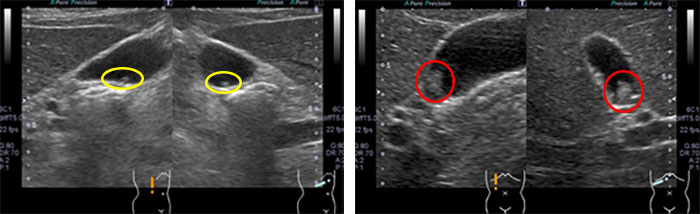

胆嚢ポリープの腹部超音波画像

右:大きめの(7~8mm)胆嚢ポリープ(赤〇)